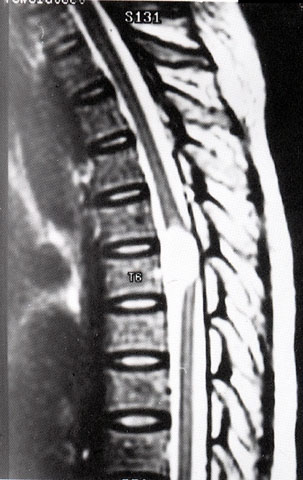

FH1084 神经鞘膜囊肿(MRI)

光盘检索编码 FH1084  函授作业图编号 1084

图  名 神经鞘膜囊肿(MRI)